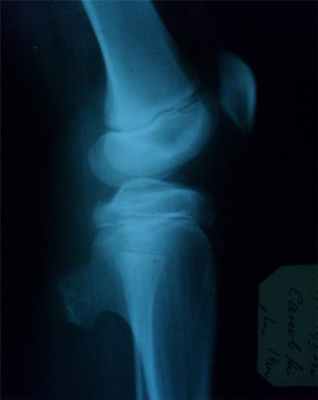

Прямая рентгенограмма таза и тазобедренных суставов.

Определяется резкая деформация тазового кольца. Правый тазобедренный сустав в норме. Выраженные изменения в левом тазобедренном суставе: суставная впадина углублена, суставная щель не прослеживается, головка деформирована с множественными очагами деструкции. Регионарный остеопороз, атрофия бедренной кости. Левосторонний туберкулезный коксит.